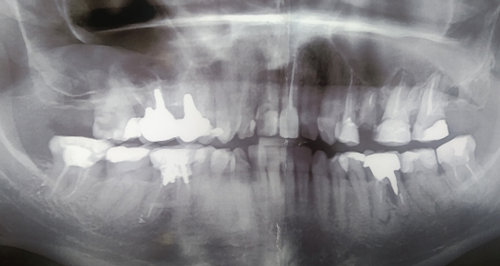

У меня зуб болит. Я его лечила 3 года назад. Мне поставили штифт в декабре 2015, он опять заболел, сделали снимок, оказалось, что он был плохо пролечен. Сняли пломбу, смогли пройти только один канал, во втором канале материал, третий мне врач не смог пройти (инструмент упирался в десну). Тогда еще врач сказал, что этот зуб только удалять, я не согласилась на удаление и мне его просто перекрыли пломбой, теперь опять побаливает.

Как думаете, нужно удалять или его еще можно спасти?

В зубе имеется перфорация, к сожалению, такой зуб спасти и сохранить невозможно.